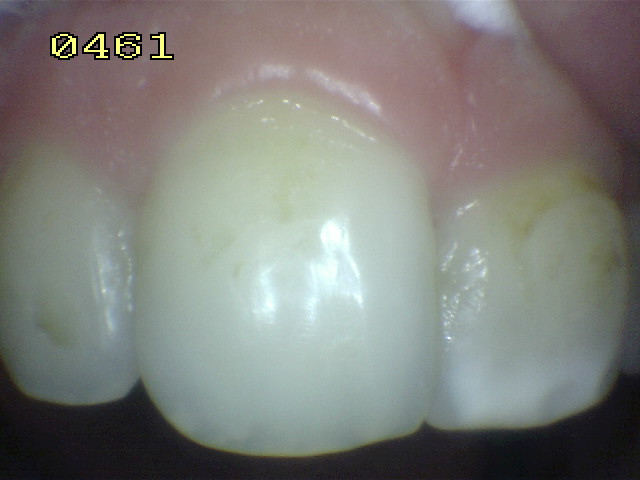

Clase III y VI

Eliminación de caries extensa en pieza dental anterior permanente con tratamiento de conducto realizado en consulta anterior, en paciente de sexo femenino de 30 años de edad.

Se observa caries  primaria en mesial  y en distal caries recurrente, con fractura del ángulo.

Vista desde vestibular donde se observa la caries mesial y distal con compromiso estético y funcional.

Aislación absoluta del campo operatorio con dique de goma y clamp cervical. se utiliza dique de goma oscura para mantener un buen contraste del campo operatorio.